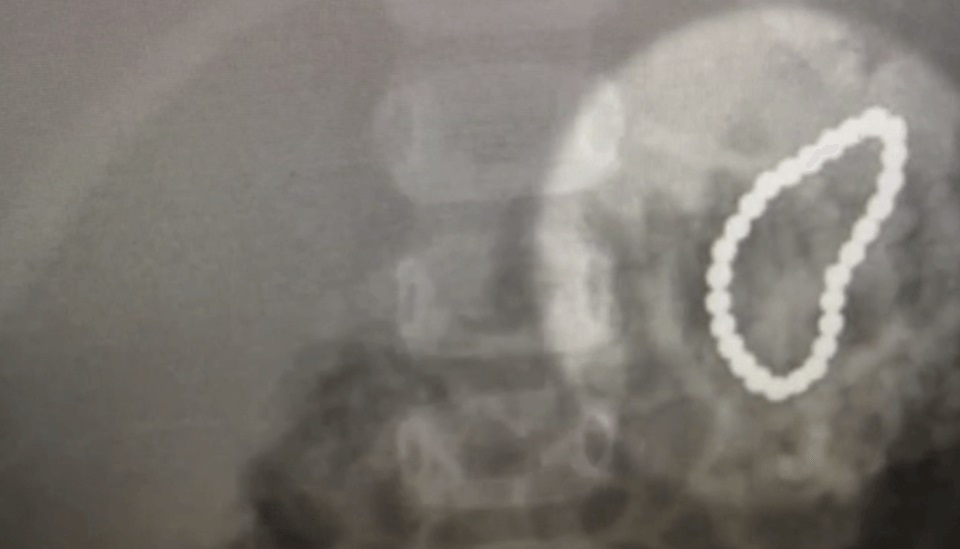

Ảnh chụp X quang cho thấy 27 viên nam châm dính lấy nhau trong bụng bé gái

Các bác sĩ tại Bệnh viện Nhi Đồng Colorado chụp X quang và phát hiện các viên nam châm nhỏ bắt đầu dính vào nhau trong bụng của bé gái.

Bác sĩ Robert Kramer tại bệnh viện cho biết: "Các viên nam châm chèn ép ruột và bắt đầu quá trình tạo một lỗ thủng trong ruột khi chúng tôi khám xét”.